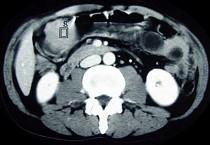

问题 女性,42岁,腹痛、黑便1周,CT扫描见胃窦部圆形块影,最佳的诊断是 ( )

选项 A.胃窦平滑肌瘤 B.胃癌 C.胃淋巴瘤 D.胃窦神经纤维瘤 E.胃内异物

答案 D